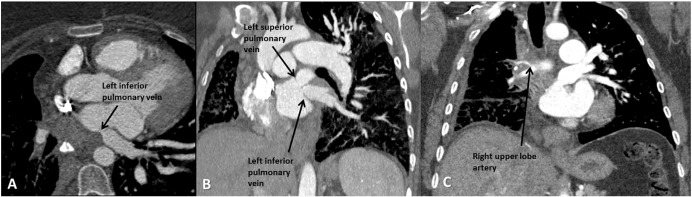

A 38-year-old woman with FM presented with six months of worsening shortness of breath and hypoxia requiring 4 L of oxygen at rest. CTA (Fig. 1) demonstrated that the right pulmonary veins were occluded, and the left pulmonary veins were stenotic but patent. Balloon angioplasty was performed in the LUPV resulting in improved symptoms. Nine months later, symptoms recurred requiring a repeat balloon angioplasty of the LLPV. At three-month follow-up, the patient was still requiring 4 L of oxygen at rest and remained dyspneic with exertion, but symptoms had improved while at rest.

Extensive involvement of fibrosing mediastinitis. (A) Transverse section of ...

Fig. 1.

Extensive involvement of fibrosing mediastinitis. (A) Transverse section of mediastinal fibrotic mass resulting in extrinsic compression of RUL artery. (B) Coronal section of stenotic left superior and inferior pulmonary veins. (C) Coronal section of mediastinal fibrotic mass resulting in extrinsic compression of RUL artery.